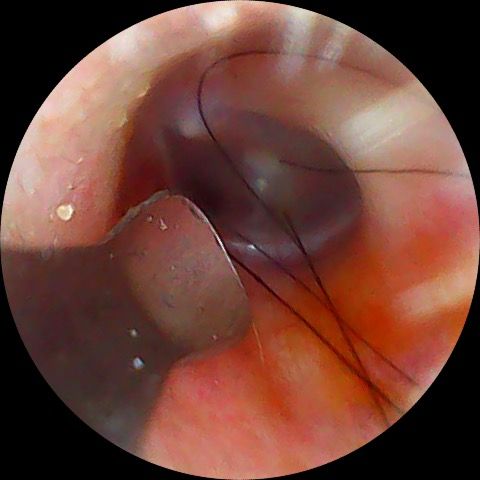

쿠팡에서 내시경 귀이개 라는 걸 발견해서

평소 습싯 귀지 때문에 귀 속이 궁금했던 차에 신기해서 사서 써봤는데

요렇게 털 같은 게 있는데 정상인가요?

다만 올려주신 사진으로 미루어 머리카락이 실수로 외이도 안쪽으로 유입된 것으로 보입니다.

사진에서 보이는 털은 외이도(귀 입구에서 고막까지 이어지는 통로)에 있는 정상적인 외이도 털로 보입니다. 외이도 피부에는 모낭과 피지선, 귀지샘이 있어 일부 사람에서는 털이 비교적 깊은 위치까지 보일 수 있습니다. 이는 이물질이나 벌레가 아니라 정상 구조입니다.

외이도 털은 귀지와 함께 먼지나 작은 이물질이 고막 쪽으로 들어가는 것을 막는 보호 역할을 합니다. 따라서 단순히 보인다는 이유만으로 제거할 필요는 없습니다. 오히려 귀이개나 내시경 기구로 반복적으로 건드리면 외이도 피부에 미세 손상이나 외이도염이 발생할 수 있습니다.